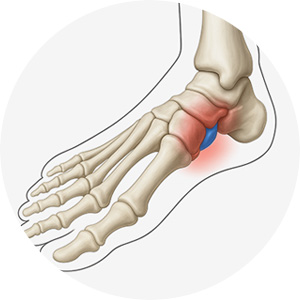

발목의 유연함을 돕는 연골이 다양한 원인으로 인해 떨어져 나간 상태를 말합니다.

움직일 때마다 뼈와 조직이 병변부위와 함께 부딪히며 통증이 발생합니다.

발목 부종

발목 소리

발목 불편감

발목 통증 부위를 누르면 통증 발생

연골 손상의 범위가 크지 않을 때 시행되는 치료로,

3mm 미만의 절개로 관절경을 삽입하여

육안으로 관절 내부를 확인하면서 진행합니다.

통증부위 아래쪽 골수를 자극하여 연골 세포의 재생을

유도하는 줄기 세포를 활용한 수술입니다.